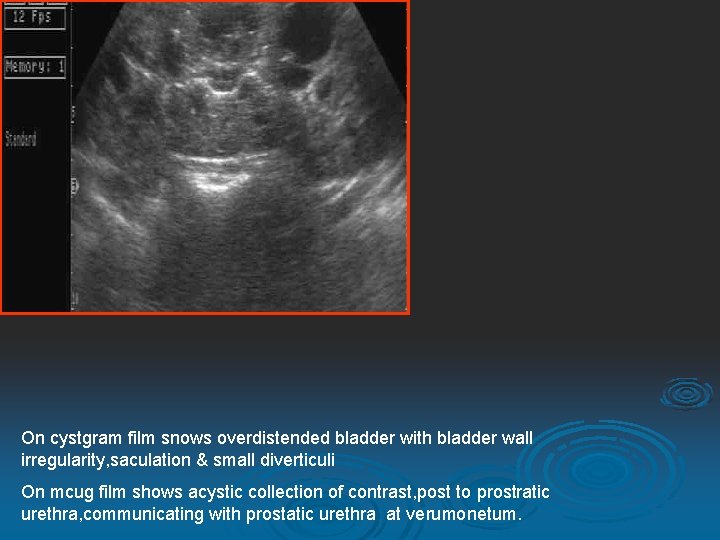

7 Yrs old boy presentated with c/o dribbling.

On cystgram film snows overdistended bladder with bladder wall irregularity, saculation & small diverticuli On mcug film shows acystic collection of contrast, post to prostratic urethra, communicating with prostatic urethra at verumonetum.

Longitudinal images of pelvis shows well denifed cystic lesion deep to the prostate.

DIAGNOSIS UTRICLE CYST

MCUG Film: shows a cystic collection of contrast post to prostatic urethra & communicating with prostatic urethra at verumontanum.

Images of the pelvis from the bladder ultrasound revealed a 3. 5 -cm midline fluid collection posterior to the bladder and superior to the prostate gland. The cystic fluid collection appears contiguous with the prostate. Echoes are noted within the cyst fluid.